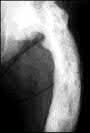

Which of the following fractures occurs through a single application of force :